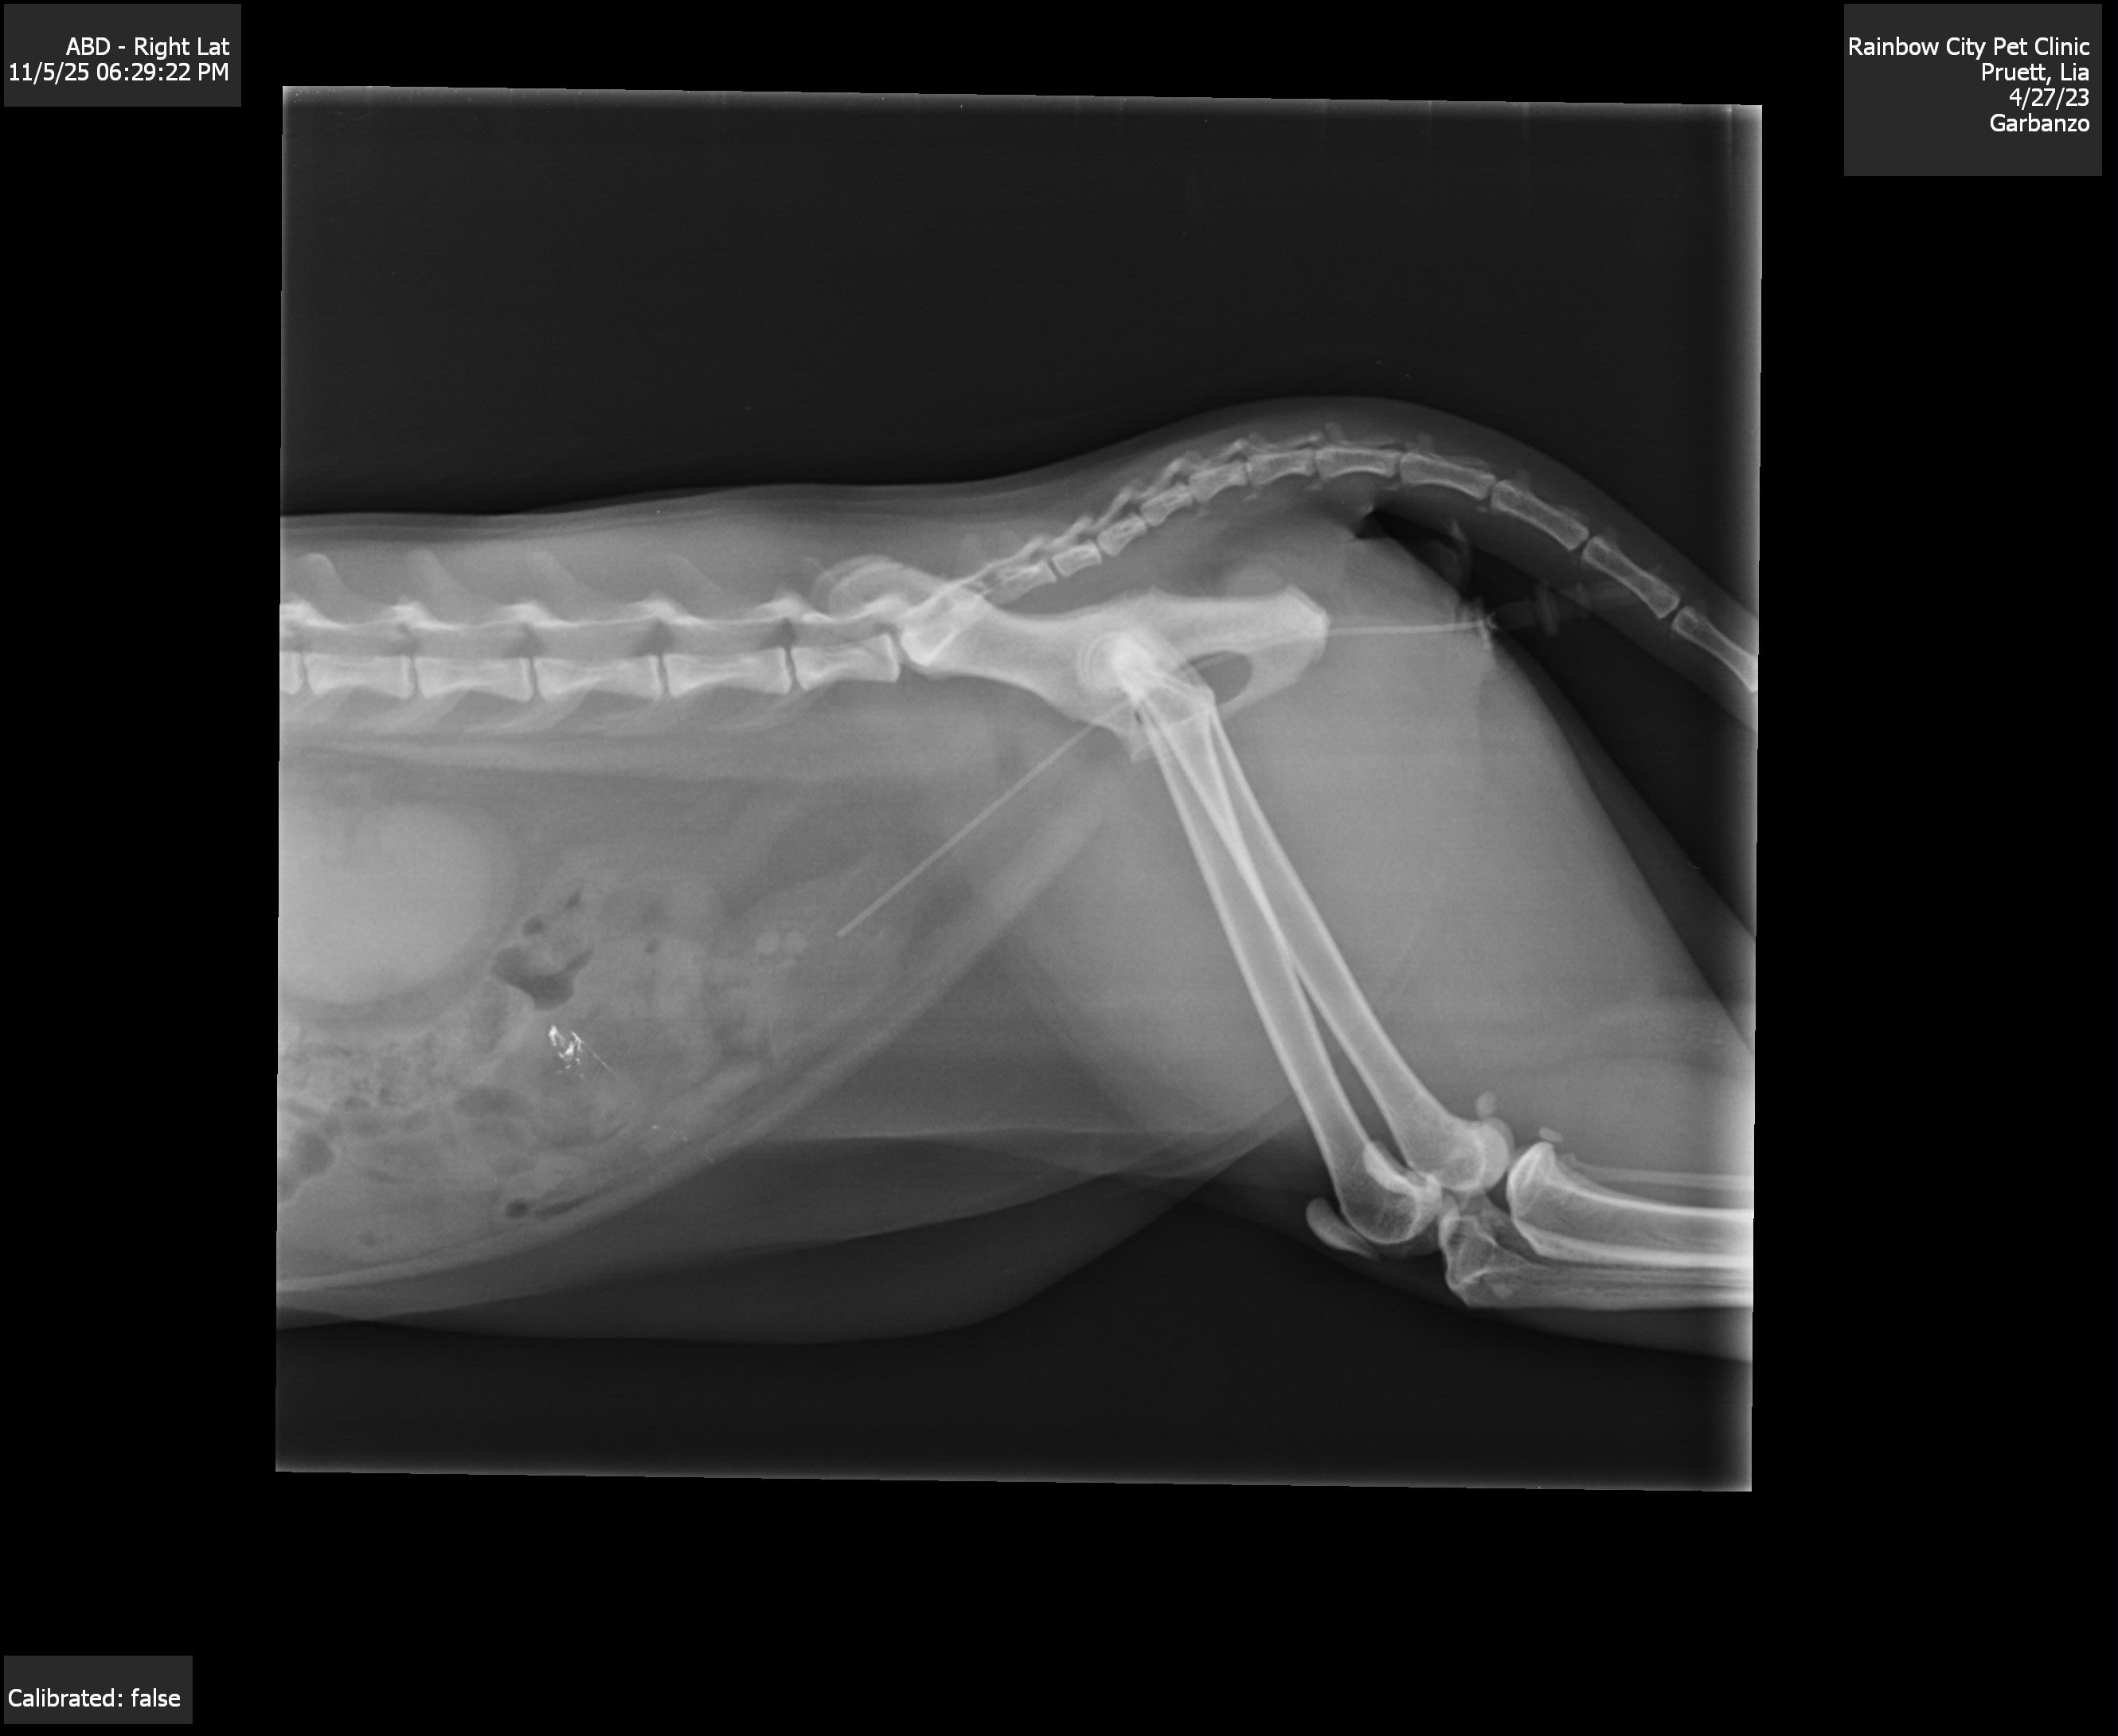

On Monday, November 3rd, Garbo went back to the vet. They discovered three stones in his bladder but assured us there was no immediate blockage. They prescribed antibiotics in hopes of them breaking them up on his own.

But by Wednesday, November 5th, Garbo's condition deteriorated drastically. He wasn’t moving, eating, or drinking. He seemed so weak and lethargic, it was heartbreaking to watch. I rushed him to the emergency vet at 2 a.m., and after a $300 emergency treatment, they drained his bladder, which was filled with bloodied urine. He was blocked.

His options are running out, and it’s looking more and more like he'll need surgery.

Surgery to remove the bladder stones.

A more drastic procedure called a Perineal Urethrostomy, which would permanently widen his urethra and allow him to urinate comfortably for the rest of his life.